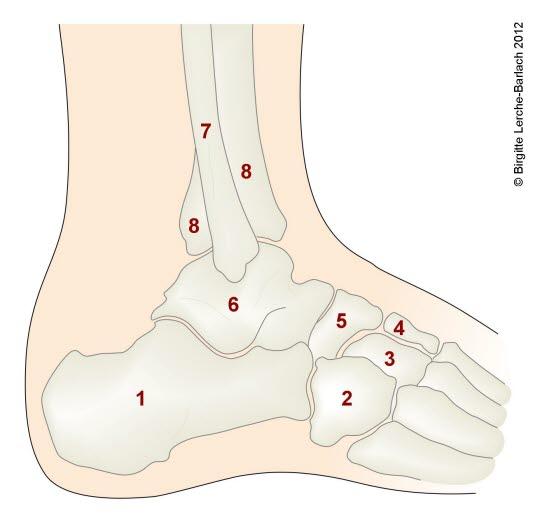

Ankelleddene er meget utsatte for skader fordi de er ganske bevegelige og belastes med hele kroppens tyngde. Leddet utgjøres av fire ben: skinnbeinet (tibia), leggbeinet (fibula), hælbeinet (calcaneus) og ankelbeinet (talus). Ankelleddet stabiliseres av ankelgaffelens form og leddbånd på innsiden (medialt), utsiden (lateralt) og mellom de to leggbeina (syndesmosen - et bånd som binder sammen de to beina). Se illustrasjon av ankelleddet nedenfor sett bakfra og fra siden, og røntgenbilde tatt skrått bakfra og fra siden.